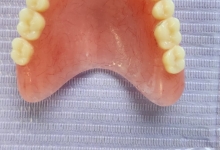

Clinica LUY ESTHETIC ART dispune de ultimele tehnologii in domeniul stomatologic si ofera solutia tratamentelor endodontice, pentru a incerca sa salveze un dinte care a fost distrus in proportii mari. Specialistii nostrii efectueaza acest tratament in mod corespunzator, pentru a evita aparitia altor complicatii ce implica interventii mai complexe: rezectia apicala sau riscul de a pierde dintele.

La Clinica LUY ESTHETIC ART tratamentul endodontic poate fi efectuat pe durata mai multor sedinte, doar cand chisturile dezvoltate sunt medii. Tratamentul nu este dureros deoarece se realizeaza sub anestezie. Pe langa talent, cunostinte medicale, dar si meticulozitate, acest tratament, presupune folosirea unei aparaturi performante: